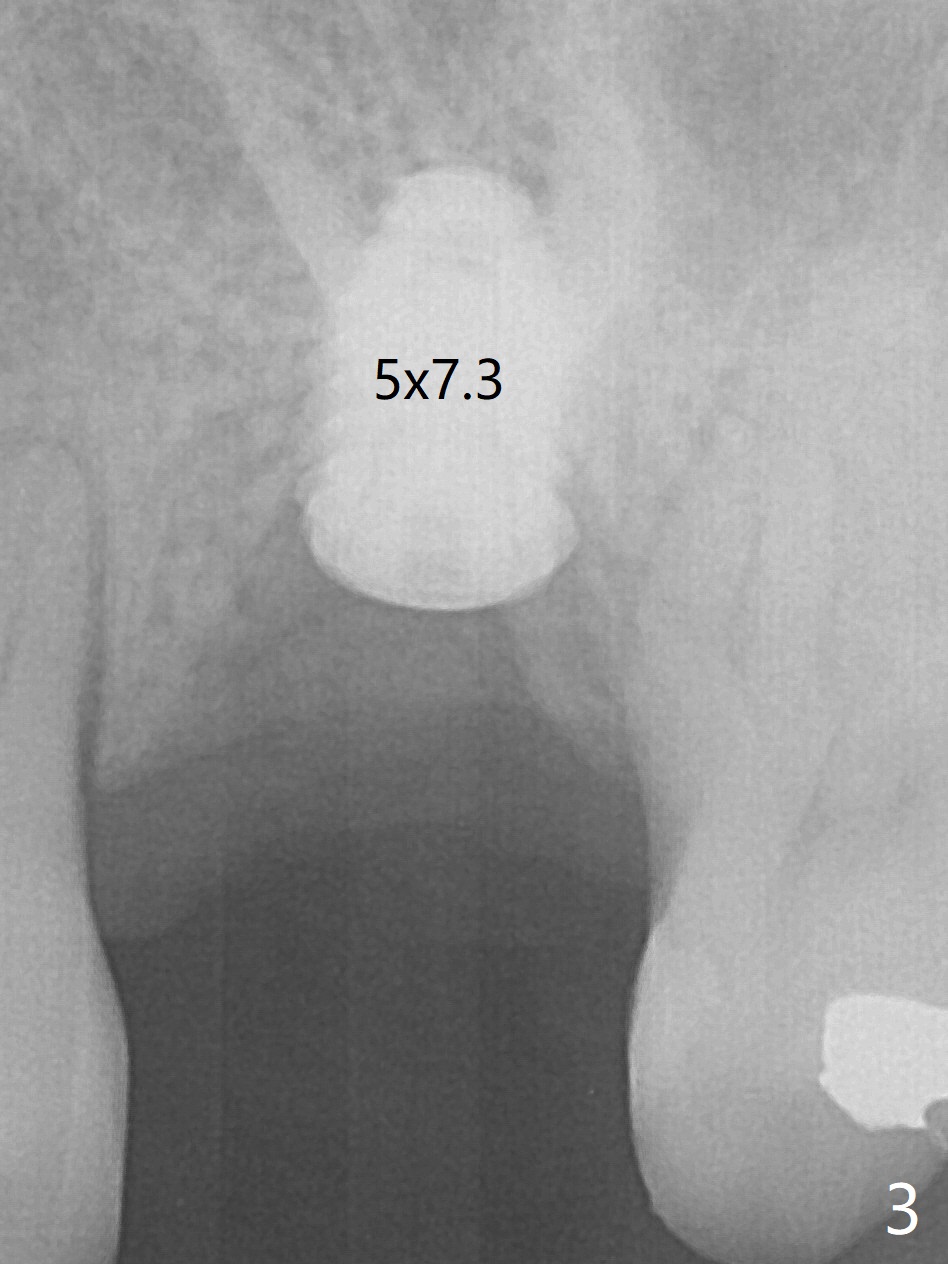

When an IBS implant with PAT surface (4.5x9 mm at #14; Fig.1 CT coronal section with ~ 7 mm bone height) is uncovered nearly 12 months postop, it is loose with a peri-implant space. Immediately post its removal and debridement, an IS dummy implant with SLA surface treatment (Fig.2: 4.5x10 mm) is placed. When a definitive implant is placed (Fig.3,4: 5x7.3 mm), it is subcrestal buccally and nearly equicrestal palatal. The remaining periimplant space is to be filled with demineralized cortical allograft. PAT: photo activated treatment (particles of calcium phosphate and a heating treatment). There is no apparent bone loss 3 months postop (Fig.5,6). The implant is uncovered with placement of a 5.7x4(4) mm cementation abutment and a nonfunctional provisional.